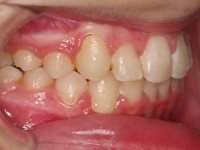

El paciente A.J. de 11 años, acude a nuestra consulta con apiñamiento maxilar importante. El canino lateral (12) está en mordida cruzada. Presenta una Clase II molar y canina, y la línea media está desviada. Se realizó un tratamiento con brackets autoligables metálicos de smartclip 022. La duración del tratamiento fue de 22 meses.

El paciente actualmente ha terminado el tratamiento con brackets y lleva una contención fija de 2-2 en maxilar y 3-3 en mandibular; para complementar también lleva una férula ESSIX durante la noche.